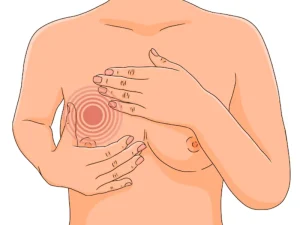

ماستیت چیست؟ اگر در این اواخر سینههای شما دچار قرمزی، التهاب، خارش و زخمهای دردناک شده است، شاید به این بیماری مبتلا شده باشید. اما

درد سینه یکی از شایعترین شکایات در میان زنان است که ممکن است در هر سنی تجربه شود. این مشکل میتواند دلایل مختلفی داشته باشد؛